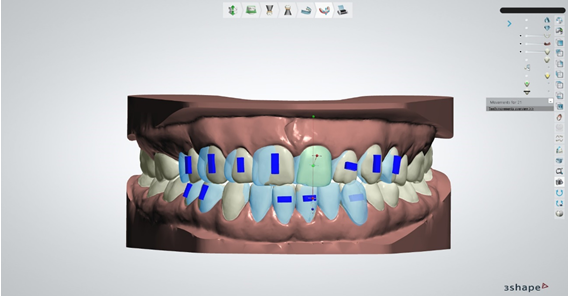

Slika 6. i 7.

Nakon odrađenih prethodno navedenih faza izrade modela I označavanja structure zuba, sustav ima dovoljno informacija da sam procijeni koja je granica anatomske krune zuba i na kojoj je poziciji gingivalni rub svake pojedine krune te isprekidanom linijom označava svaki pojedini zub. Ovdje moramo dobro iskontrolirati liniju koju je sustav označio I po potrebi je korigirati da linija obuhvaća zub u što je većoj mjeri moguće. Ako nismo zadovoljni sa onim što je algoritam odredio ili ćemo point editom ili free formom prepraviti rub te nakon toga stisnuti kalkulaciju. Nakon kalkulacije, sustav će segmetirati svaki pojedini zub I u digitalnom dizajnu ga razdvojiti na više manjih stl fileova koji predstavljaju svaki pojedini zub I bazu modela bez zuba

Slika 8. Ako smo zadovoljni sa segmentacijom zuba, obavezno proučavamo uputstva ortodonta koji bi nam morao dati točnu informaciju na kojim zubima i na kojim pozicijama želi da postavimo tzv. attachmente. Attachmenti su mali kompozitni oblici koji se apliciraju na zube koje je ortodont procijenio da su najoptimalniji za postavu attachmenta. Oni u kombinaciji sa udlagom znatno pospješuju pomake zuba te s njima možemo očekivati bolje, stabilnije I brže rezultate. Oblik attachmenta može biti raznoliki i također ovdje ortodont mora odabrati oblik attachmenta koji mu najviše odgovara. Također postoji i mogućnost dimplingsa koji umjesto attachmenta koji se lijepe na zub služe kao negativi u udlagi koji jače guraju zub u željenom smjeru.